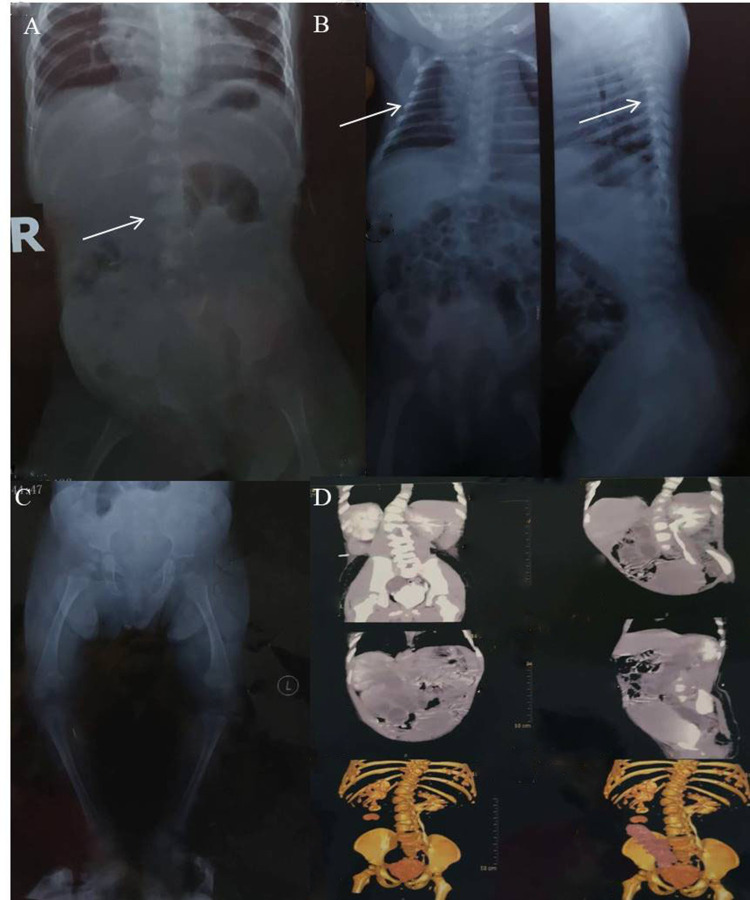

Objective: To describe the clinical manifestations and genetic mutation in a 7-year-old girl presenting with severe scoliosis, hydronephrosis, and other skeletal abnormalities.

Results: Exome sequencing revealed a de novo EBP mutation (c.452A>G, p.Gln151Arg) in the patient.

Conclusion: The patient was diagnosed with X-linked chondrodysplasia punctata type 2 (CDPX2). This novel missense mutation expands the mutation spectrum of CDPX2 and underscores the clinical utility of exome sequencing in diagnosing this condition.